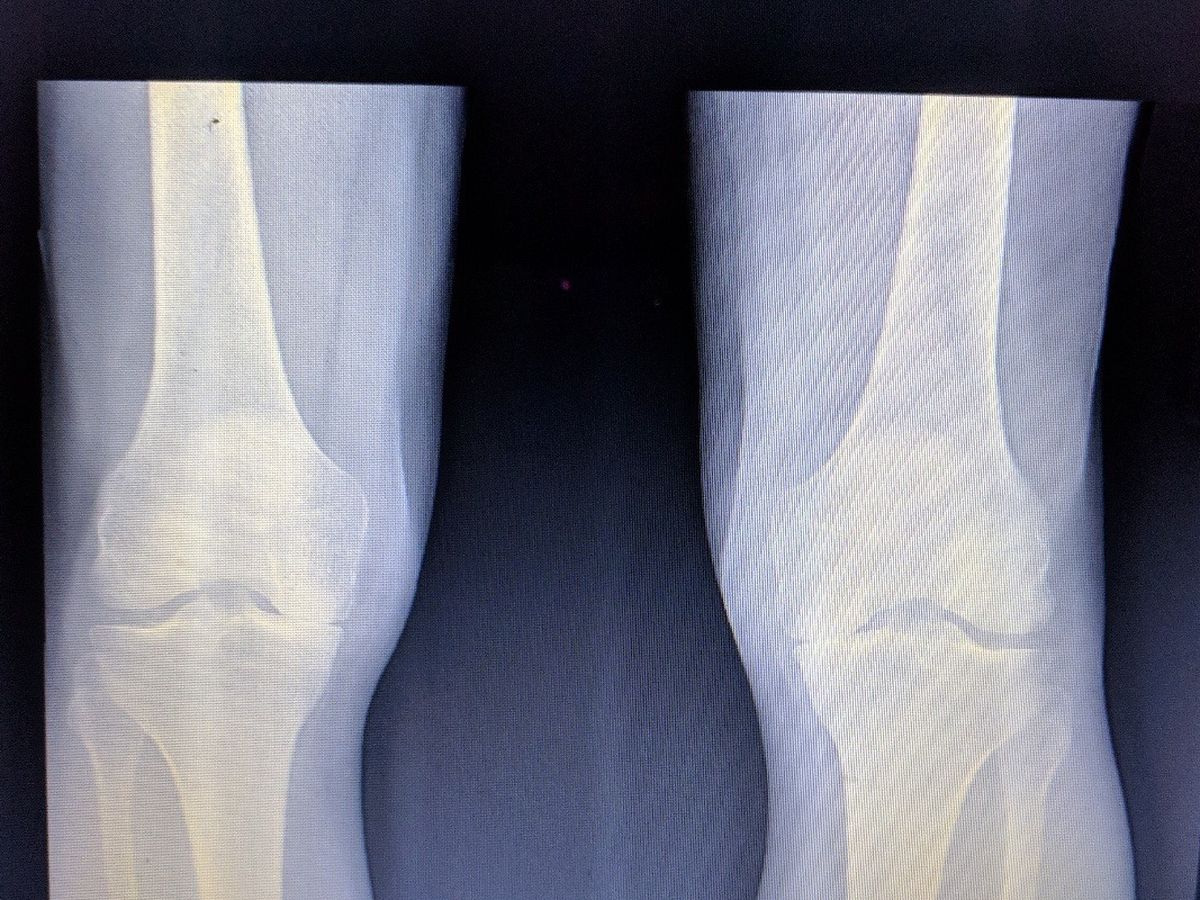

Please allow me a moment to be vulnerable as I struggle through the shame and fear that is associated so often with “vulnerability.” I will borrow from the knowledge and eloquence of Brene Brown and Jeremy Deaton. “Vulnerability is the core of shame and fear and our struggle for worthiness, but it appears that it’s also the birthplace of joy, of creativity, of belonging, of love.” Brene Brown “A request for help may feel like a sign of weakness—we generally avoid seeming inadequate, incompetent, or needy. Americans, in particular, place a premium on self-reliance, and it can be difficult to overcome the pressure to go it alone. Rather than viewing vulnerability as a marker of weakness, we can choose to see it as a sign of strength. It takes a lot of courage to ask for help, which is a fact we often recognize in others before ourselves. When a friend reaches out to you, do you refuse to help, or greet them with open arms?” Jeremy Deaton. As many of you know I had partial knee replacement (left) on March 8th and I will undergo partial knee replacement (right) in approximately 4 weeks (insurance is still “reviewing” however I have excellent doctors fighting for approval to go forward with the procedure.) One of the mistakes that I have made is that I failed to ask for help earlier.  I have not received disability benefits or a dime of income since March 6th, 2018.  I have not been able to drive for Lyft due to a block on my expired registration. I have spoken with Texas Toll Authority to work out a payment plan on unpaid tolls that I uncured (which I take responsibility for); however at this time I cannot execute the payment plan which would release my registration block because I can’t afford the initial payment. I have fallen behind on my rent and now eviction is looming and I will be served with eviction papers on April 10th.  I have been told I will have approximately 7-14 days before I will have to appear in court; once I appear in court there is no turning back and I will be forced to leave.  If I am able to settle my rent with late fees and eviction filing charges prior to the court date, I will be able to stay in my apartment; the apartment manager has stated that there is a possibility that I can relocate to a smaller apartment if a I am able to settle my balance prior to court.    I am overdrawn $1540 on my checking account as I had to pay for my deductible and medical expenses at the time of my surgery. (I did not intentionally overdraw my account which some of you know the circumstances surrounding that.) Thank you for taking the time to read this. Doug Sharp